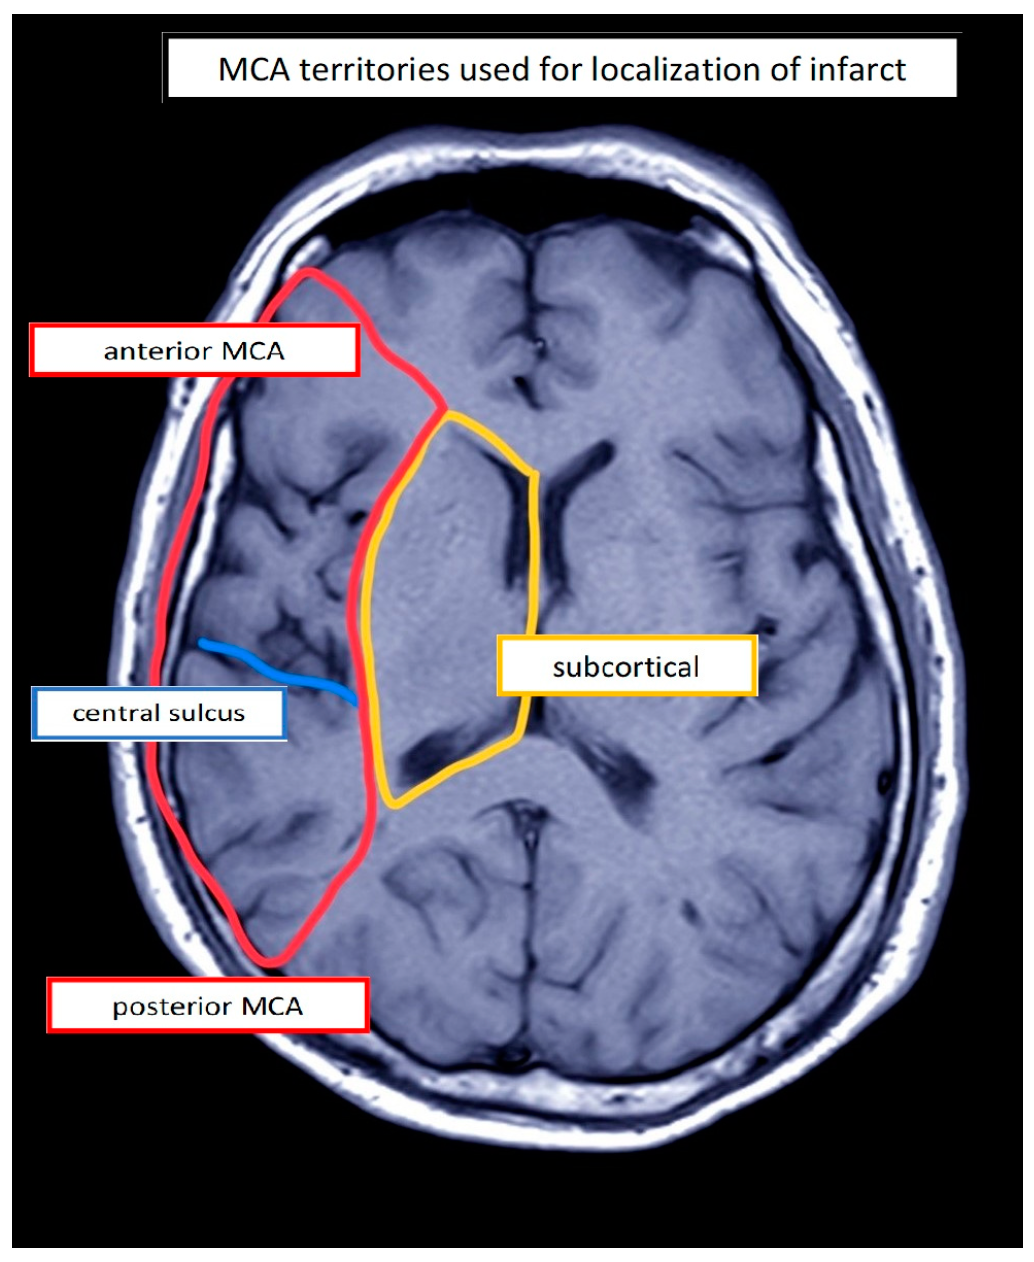

| PwA | Etiology | Lesion Location 1 | Stimulation Site (Left) | Sex | Age (Years) | Education (Years) | Duration (Days) | Assessment | Aphasia 2 | Aphasia Severity 3,4 | Initial Severity (ERBI) 5 (FIM) 6 (−325 to +105) (18–126) | |

| 1 | IS | a/sc | IFG | M | 58 | 18 | 25 | AAT | Wernicke | Moderate 2 | 55 | 102 |

| 2 | IS | a | IFG | F | 82 | 10 | 33 | AAT | Wernicke | Mild | 40 | 62 |

| 3 | IS | a | IFG | M | 70 | 16 | 21 | AAT | Wernicke | Severe | 25 | 68 |

| 4 | IS | sc | IFG | M | 66 | 17 | 57 | AAT | Anomic | Mild | 60 | 86 |

| 5 | IHS | sc | IFG | F | 63 | 16 | 29 | AAT | Anomic | Mild | −15 | 47 |

| 6 | IHS | p/sc | IFG | F | 57 | 17 | 25 | AAT | Anomic | Residual | 40 | 107 |

| 7 | IS | a/p | IFG | M | 69 | 16 | 107 | AAT | Wernicke | Moderate | 50 | 79 |

| 8 | IHS | a/sc | FPC | M | 41 | 16 | 77 | AAT | Anomic | Moderate | −15 | 81 |

| 9 | IHS | p | IFG | M | 64 | 13 | 47 | AAT | Wernicke | Moderate | −65 | 70 |

| 10 | IS | a | IFG | F | 64 | 13 | 13 | AAT | Global | Severe | 5 | 107 |

| 11 | IS | a/sc | IFG | M | 52 | 17 | 32 | AAT | Global | Severe | 35 | 92 |

| 12 | IS | sc | IFG | M | 36 | 12 | 29 | AAT | Global | Severe | 45 | 89 |

| 13 | IS | a/sc | IFG | M | 71 | 13 | 55 | AAT | Broca | Mild | −30 | 53 |

| 14 | IS | a/sc | IFG | M | 48 | 17 | 15 | AAT | Broca | Severe | 60 | 84 |

| 15 | IS | a/p | IFG | M | 73 | 17 | 16 | AAT | Wernicke | Severe | 10 | 93 |

| 16 | IS | sc | IFG | F | 62 | 17 | 46 | AAT | Global | Moderate | −20 | 52 |

| 17 | IS | sc | IFG | M | 50 | 17 | 99 | AAT | Broca | Mild | 10 | 80 |

| 18 | IS | sc | IFG | M | 58 | 10 | 83 | AAT | Global | Severe | 30 | 46 |

| 19 | IS | a | IFG | F | 67 | 10 | 56 | AAT | Anomic | Mild | 15 | 60 |

| 20 | IS | a/p | IFG | M | 66 | 10 | 64 | AAT | Global | Severe | −10 | 47 |

| 21 | IS | a | IFG | M | 69 | 13 | 102 | AAT | Broca | Moderate | −15 | 29 |

| 22 | IS | p | IFG | F | 81 | 10 | 66 | AAT | Wernicke | Severe | 25 | 92 |

| 23 | IS | a | IFG | M | 50 | 16 | 41 | AAT | Broca | Severe | 30 | 81 |

| 24 | IS | sc | IFG | M | 62 | 12 | 24 | AAT | Broca | Moderate | 55 | 95 |

| 25 | IS | a/sc | IFG | M | 60 | 9 | 85 | AAT | Wernicke | Moderate | 5 | 64 |

| 26 | IS | a | IFG | F | 83 | 13 | 31 | AAT | Wernicke | Moderate | 50 | 84 |

| 27 | IS | a/sc | IFG | M | 51 | 16 | 54 | AAT | Wernicke | Moderate | 0 | 90 |